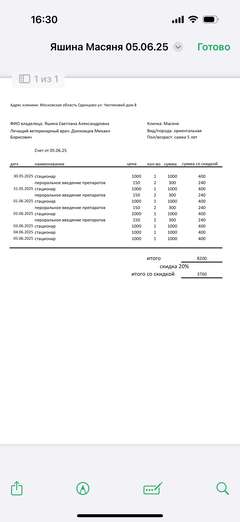

Ярко выраженная болезненность в области крестца, на обезболе полегче. По результатам приема невролога проведена миелография - множественная компрессия, возможно опухоль, возможно грыжа, нужно удалять...

Баланс на 12.06.2025: минус 32 396,34